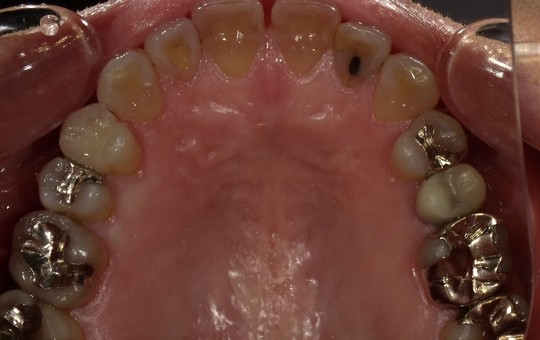

前歯の審美修復

臼歯の審美修復

歯の着色、ステイン除去